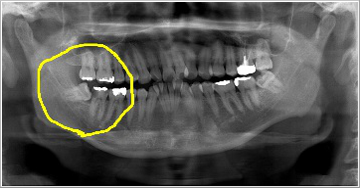

これは横向きに出てきた親知らずとその前の歯との間に食べ物が詰まり、取れなくなった為に奥の方まで炎症が広がり、結果的に前の歯を抜かなければならなくなった症例です。 この患者さんは「右下奥歯が動き出し、痛くて噛めなくなりました」といって来院されました。

親知らずは虫歯にならず、その前の歯だけに大きな虫歯を造っている親知らずもあります。